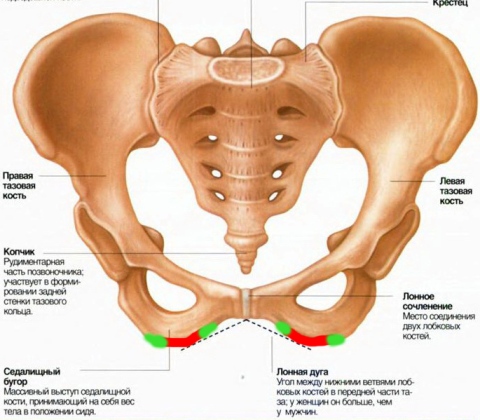

Анатомия малого таза: детальные схемы и изображения